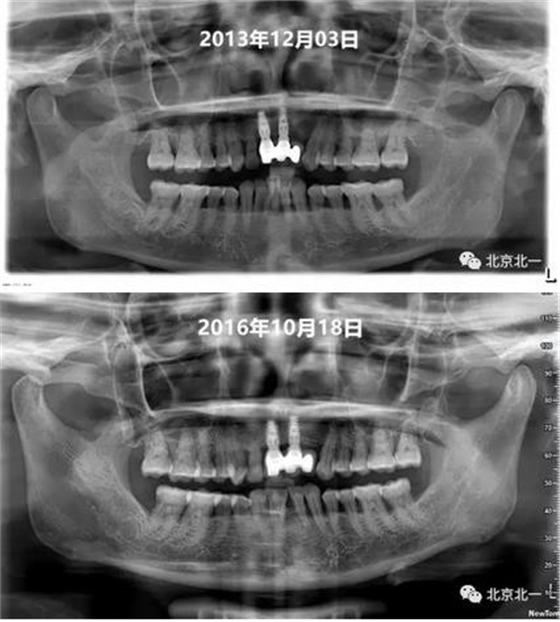

圖十、圖十一:2013年到2016年比較X片,骨平面很穩(wěn)定。牙齦及牙周黏膜健康,區(qū)別在于2016年時(shí)候31牙位缺失。